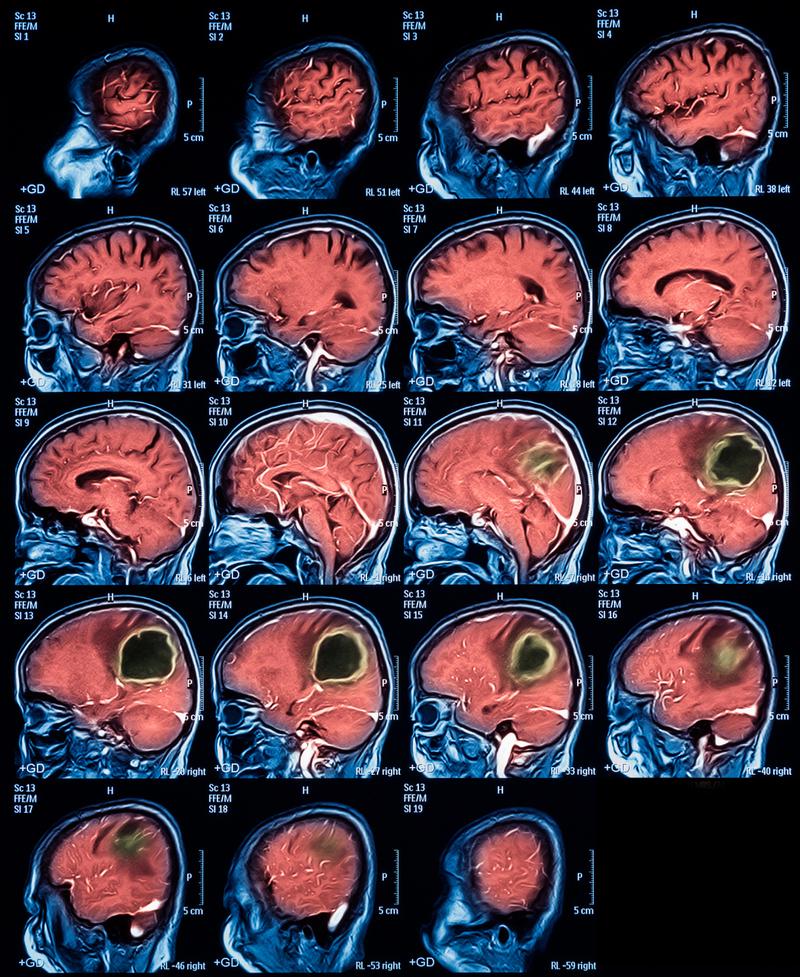

(图片来源网络,侵删)

脑梗塞(较大动脉梗塞)

这是指大脑的主要供血动脉(如大脑中动脉、颈内动脉等)被血栓堵塞,导致其供应的大片脑组织缺血坏死,梗塞灶通常较大。

CT表现特点:

- 病灶位置:

- 符合大脑主要动脉的供血区。

- 大脑中动脉供血区:最常见,累及大脑外侧、颞叶、顶叶等大片区域。

- 大脑前动脉供血区:累及额叶内侧。

- 大脑后动脉供血区:累及枕叶(视觉中枢)和颞叶下部。

- 病灶大小:

- 范围大,呈片状或楔形的低密度影,占据大脑的一个“扇形”区域。

- 病灶形态:

形态不规则,范围广,边界可能模糊(早期水肿时)。

- 占位效应:

- 非常明显! 大面积的脑组织水肿和坏死会像“水肿”一样挤压周围组织,导致:

- 脑沟变浅或消失。

- 脑室受压变形、变窄。

- 脑中线结构(如中线隔)向对侧移位,这是脑梗的危急信号,可能危及生命。

- 时间窗(超急性期/急性期):

- 发病6小时内,CT可能完全正常,这就是为什么对怀疑脑梗的患者要尽快做CTA(CT血管造影)或MRI-DWI来早期发现血管堵塞和缺血。

- 发病6-24小时后,CT开始显示边界模糊的低密度区。

- 发病1-2天后,低密度区变得非常清晰,同时水肿和占位效应最明显。

一句话总结较大脑梗CT: 大脑主要动脉供血区的大片状、有明显占位效应(脑中线移位等)的低密度影。